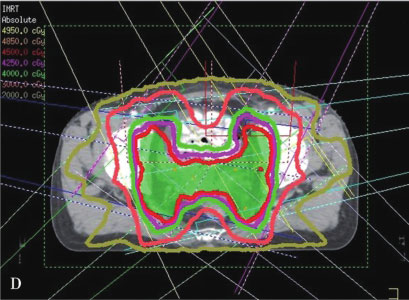

IMRT则是在3DCRT基础上的进一步发展,自1990年代早期IMRT被应用于临床以来,目前已成为一项常规开展的技术。IMRT通过多角度射野设置、多子野分割、滑窗等技术使均匀输出的通量分布变成不均匀分布,明显增加了靶区的剂量适形性,以避免或减少正常组织的照射,最大限度地限制治疗的副作用。IMRT的主要优势是其对凹凸靶区的适形能力,特别是凹面邻近重要器官时尤有优势。据估计,临床治疗的PTV有30%是凹形的靶区,因此可以从IMRT明显获益。另一方面,IMRT治疗方案是在治疗计划系统内通过逆向治疗计划的设计而得到,可以获得较正向计划方法更优的靶区适形性和更窄的侧向半影。通过调节每个射野的通量强度,在肿瘤靶区和正常器官之间形成一个很窄的剂量梯度,通常允许至少95%的PTV接受规定的处方剂量,同时保证周围正常组织的受量在既定的耐受范围之内。图7-2-1为IMRT与3DCRT技术的剂量分布图,其中图A、B、C所示为3DCRT剂量分布,图D、E、F所示为IMRT剂量分布,其中IMRT的剂量靶区适形性明显优于3D-CRT。

图7-2-1 IMRT与3DCRT技术的剂量分布图

A~C.为3DCRT剂量分布;D~F.为IMRT剂量分布